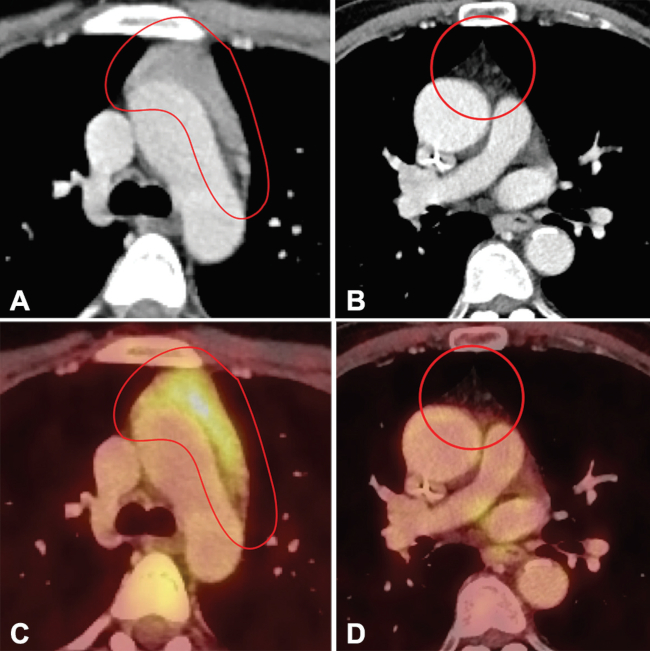

Normalmente, la captación tímica fisiológica es de baja intensidad. Los valores máximos de captación (SUVmáx) del timo normal se han situado entre aproximadamente 1,0 y 1,8, aunque existe un cierto grado de traslape entre esos valores y los que se encuentran en la hiperplasia tímica (►Fig. 1).4

Aunque los dos tipos de hiperplasia tímica son imposibles de diferenciar mediante imágenes, la hiperplasia tímica generalmente puede distinguirse de procesos expansivos en base a ciertos hallazgos orientadores. La hiperplasia tímica generalmente se presenta como un aumento difuso y simétrico de volumen tímico, de contornos suaves, con densidad intercalada de grasa y de partes blandas, manteniendo los planos grasos de clivaje (►Fig. 2). En contraste con lo anterior, un tumor tímico puede demostrar una masa focal, contornos nodulares, heterogeneidad (que representa hemorragia o necrosis) y/o calcificaciones.7 Los valores SUVmáx de 18F-FDG en hiperplasia tímica se sitúan aproximadamente entre 2,0 y 2,8.2 Se puede emplear la imagen de RM por desplazamiento químico (chemical shift). Así, en la hiperplasia tímica, podemos observar una caída de señal en las imágenes fuera de fase respecto de las imágenes en fase, debido a la presencia de grasa microscópica en el timo hiperplásico (►Fig. 3).8